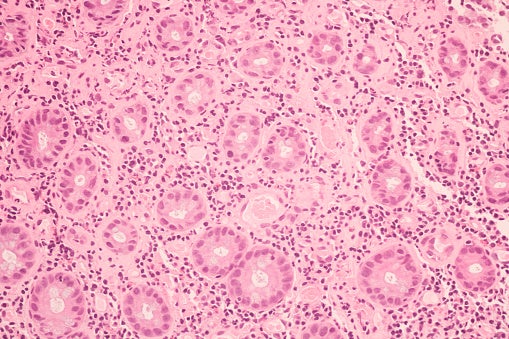

Breast BiopsyWhen a woman finds a lump in her breast, it can be scary, but certain tests can help her find out quickly if something is really wrong, or if the lump is nothing to worry about. A breast biopsy is one of those tests.A breast biopsy is a procedure to take a sample of breast tissue. A biopsy is done when a woman or her healthcare provider finds a lump in her breast during an exam or spots one on an imaging test.During a biopsy, some tissue is taken from the lump and examined in a lab. In some cases, the whole lump is removed. Types of Biopsies.Your healthcare provider will talk with you about the type of biopsy that'll work best for you.With a fine needle biopsy, or FNA, the skin is numbed, and a thin needle is put through the skin of the breast into the lump. A small amount of tissue is taken from the lump.With a core needle biopsy, a larger needle is used so that a larger amount of tissue can be taken.These two procedures are often done in a doctor's office or clinic.Sometimes, a needle biopsy is done while the healthcare provider uses an imaging machine to guide the needle. The imaging may be a mammogram, ultrasound machine, or MRI. This is called a stereotactic biopsy. This procedure is often done in a hospital.In some cases, a needle biopsy is not possible, or it may not give the healthcare provider enough tissue. If this is the case, an open biopsy may be done. An open biopsy is often done in a hospital or surgery center.Before the procedure, you're given anesthesia. It will make you relaxed, drowsy, or asleep during the procedure. An incision is made in the breast. A piece of tissue from the lump is removed. This is called an incisional biopsy.If the whole lump is removed, this is called an excisional biopsy. It's also known as a lumpectomy.Often, a guidewire will be placed in the breast. X-rays are used to direct the healthcare provider to the area of tissue to be sampled. This is called a needle-directed biopsy or J-wire directed biopsy.After the tissue is removed, a tiny marker or clip may be inserted in the site so that the area can be monitored with x-rays to check for changes.When the biopsy is finished, the incision is closed with sutures or adhesive strips. A bandage is put over the area.After your biopsyAfter your biopsy, keep the bandage clean and dry. Change or remove the bandage as your healthcare provider advises.After bathing, gently pat the incision area dry. Don't rub or pull on the incision site.You may see a bruise at or around the site. This is normal.The incision will heal on its own in a week or two.You'll probably have some pain in your breast for a day or two after your biopsy. You may be instructed to apply an icepack to the biopsy site periodically to relieve pain and swelling.Ask your healthcare provider about taking pain medication, and make sure to ask your healthcare provider about the symptoms of infection. These include fever or chills, or redness, swelling, or worse pain in the breast.In the meantime, your tissue sample will be sent to a lab. There, a pathologist will examine the tissue and make a diagnosis. It may take a week or more to get the results of your biopsy.Make a follow-up appointment with your healthcare provider to learn about your results. He or she will go over any additional tests you may need or help you set up a treatment plan.Things to rememberYour healthcare provider will help you decide on the type of biopsy that's best for you.Anesthesia will be used to prevent discomfort during the biopsy.Follow all instructions on caring for your incision and the biopsy area.In a week or two, your healthcare provider will talk with you about your results.A breast biopsy is an important type of test that can give more information about your health. Make sure to ask your healthcare provider if you have any questions or concerns.What we have learnedA fine needle biopsy requires an overnight stay in the hospital. True or False?The answer is False. A fine needle biopsy can often be done in a doctor's office.In an open biopsy, sometimes the entire lump will be removed from your breast. True or False?The answer is True. This is called an excisional biopsy or a lumpectomy.Breast biopsy results are available right away. True or False?The answer is false. It may take one or two weeks to get the results of your biopsy.